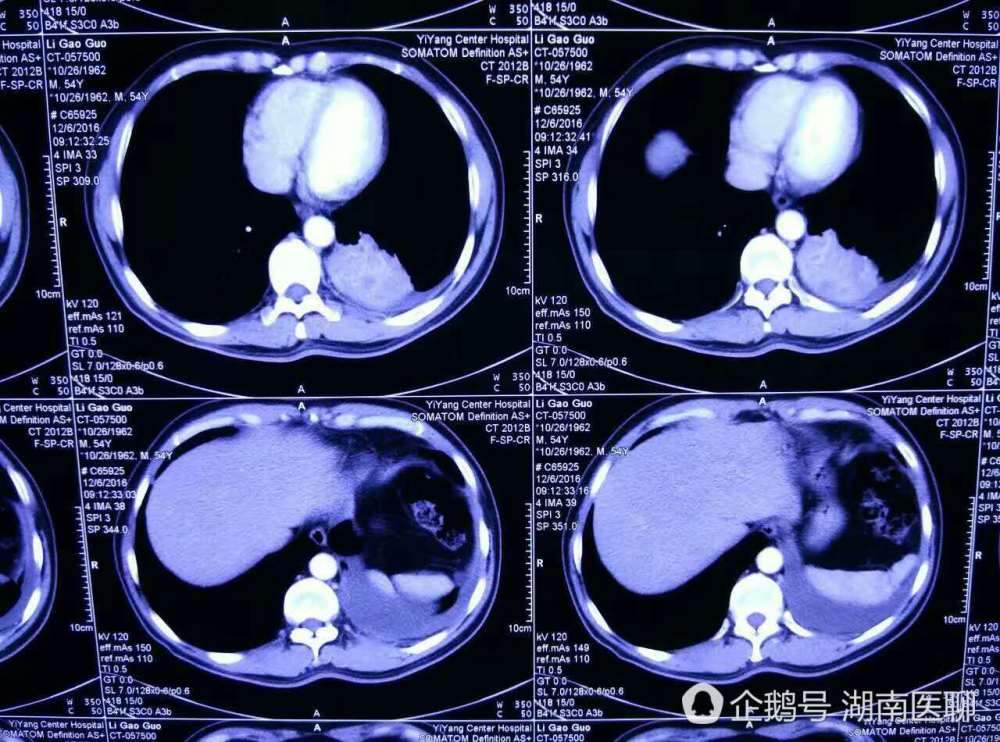

男子反复咳嗽咳痰 原是支气管里 辣椒尖 作祟